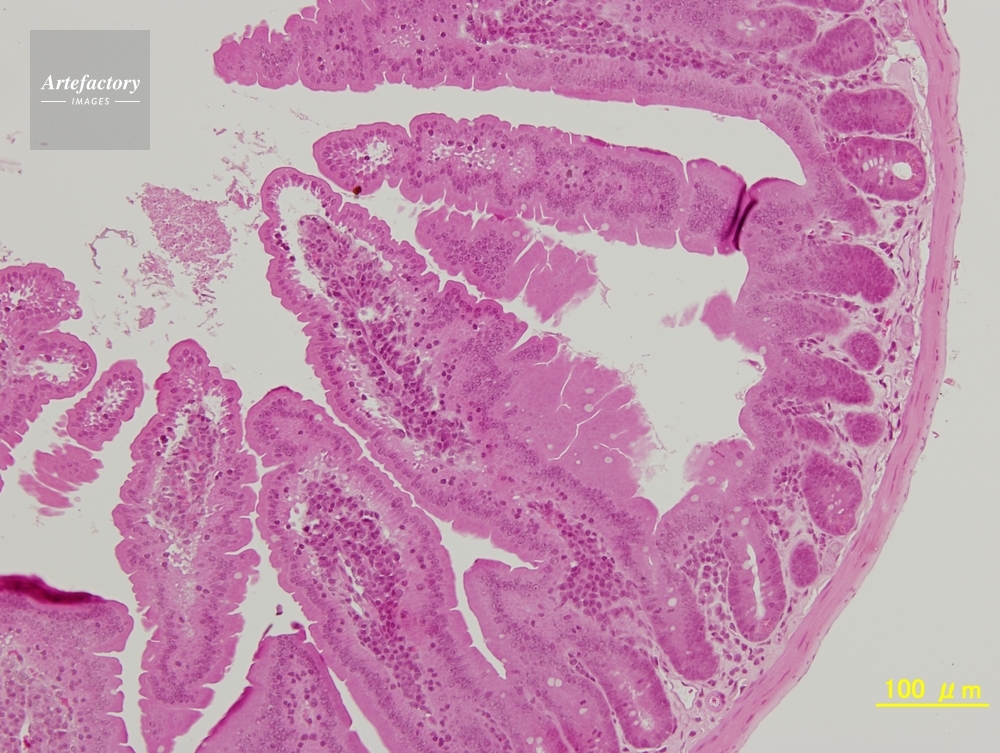

| 作品タイトル | マウス,十二指腸 | モデルリリース | なし | |

| 作家 | OLYMPUS CORPORATION Technolab | プロパティリリース | なし | |